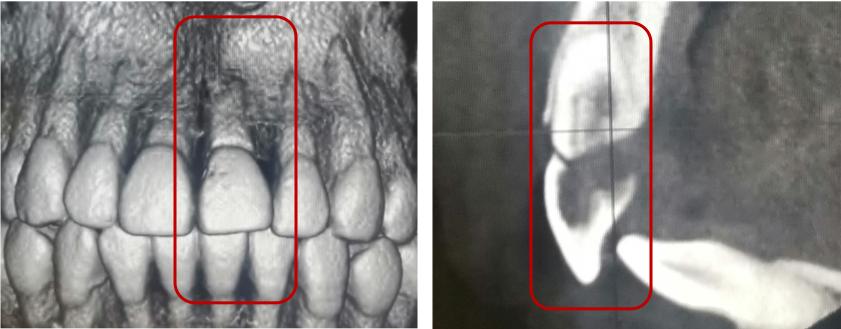

根折--根中1/3

治疗方案:复位松动移位的牙冠,夹板固定4周,定期检测折断线愈合情况,监测牙髓状态。牙髓坏死或感染则进行冠方的牙髓治疗。